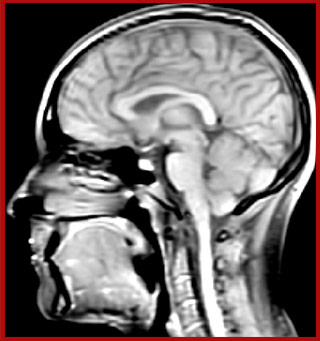

Myelin water imaging (MWI) is a breakthrough technique that was pioneered at UBC for measuring myelin content in the brain, in vivo. “Because the T2 time of water in myelin is much shorter than the T2 of water in the intraand extracellular spaces, we can separate out the myelin water signal.”

The techniques for measuring myelin have changed a lot over the years. “Since we are using the Elition, our myelin water images are much better. We're now acquiring 1 x 2 x 5 mm voxels and displaying at 1 x 1 x 2.5 mm. For a whole brain we can now measure the fraction of water in the myelin component in only about five or six minutes,” Dr. MacKay says.

of limiting MWI to the brain, even without the cerebellum, we can now spend about the same amount of time and scan the whole brain and the cervical spinal cord, which is a huge boost for us.” Dr. Rauscher says, “For MWI we perform 3D T2 with 32 or more echoes. This used to take a long time, but with Compressed SENSE we can decrease this to ten minutes for the whole head. Because of the large field of view (FOV) on the readout direction, we even get information from the brainstem, which we previously missed when we were using the GRASE approach. Having the whole head scan is nice because it has spatial resolution, orientation and FOV that are comparable to the standard 3D clinical MS scans, including the FLAIR and 3D T2, and a 3D T1 for brain volume.”

T1 - Weighted, Myelin Water Fraction Superimposed

Spinal cord coverage

Smaller, more isotropic voxels

Excellent detail in quantitative maps

Images courtesy of Adam Dvorak, Department of Physics and Astronomy, University of British Columbia